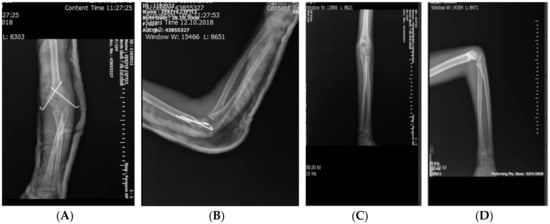

2.1. Surgical Technique